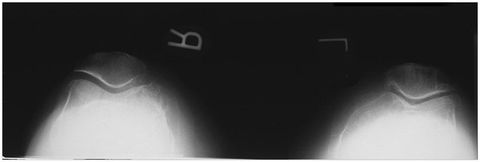

A. patella B. femoropatellar joint C. lateral condyle D. patellar surface E. medial condyle

Merchant Bilateral Method Patella pt seated with knees flexed 40 degrees on merchant board - CR angled 30 degrees caudal @ midway between the patellae *over flexion of knees will pull the patellae into the trochlear groove*

Inferosuperior Bilateral Patellae Sunrise 40-45 degree flexion of knees - CR angled 10-15 degrees cephalic from perpendicular @ femoropatellar joint